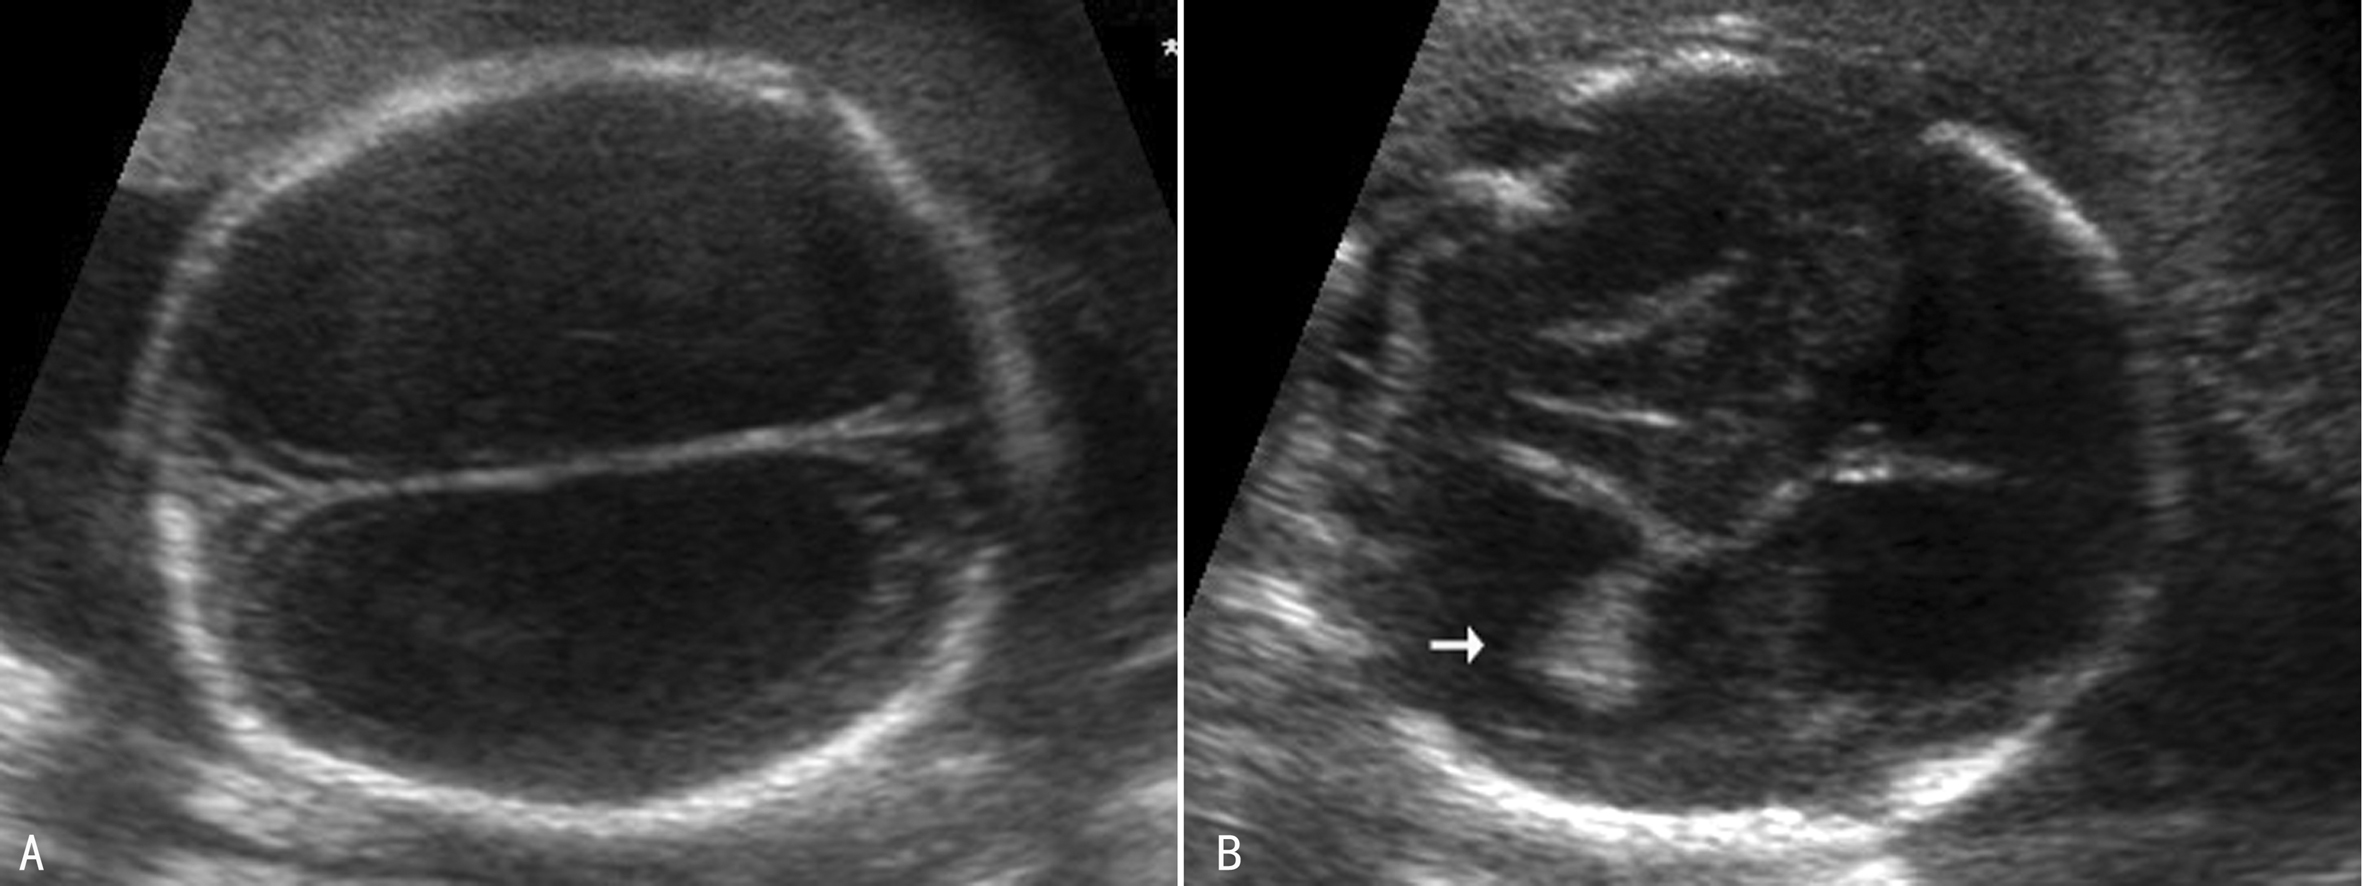

3.重度脑室增宽 重度侧脑室增宽(SVM)俗称HC(图3)。超声显像检查可以显示为对称性脑室扩张(图3,图4A),也可以显示为非对称性脑室扩张(图4B),严重时颅内完全由无回声的积液占据,脑组织显示不清。重度侧脑室增宽最常见的原因是中脑导水管硬化,并且有60%的胎儿伴有CNS结构异常,包括前脑无裂畸形、Dandy-Walker畸形、脊柱裂、小脑扁桃体下疝畸形、脑穿通畸形等,但较少合并染色体异常。超声显像检查显示胎儿头颅增大,脑室系统扩张,压力升高,脑室周围灰质、白质相继受压,严重时颅内结构不可辨认或显示不清,神经结构及功能严重受损,胎儿出生后多有严重的智力障碍。

图3胎儿脑积水声像图,剪头示脉络膜悬吊于脑室内

(2)脉络丛活动:常见于侧脑室严重增宽时,显示为脉络丛非常薄或者脉络丛自由地飘浮在脑室中(图3)。